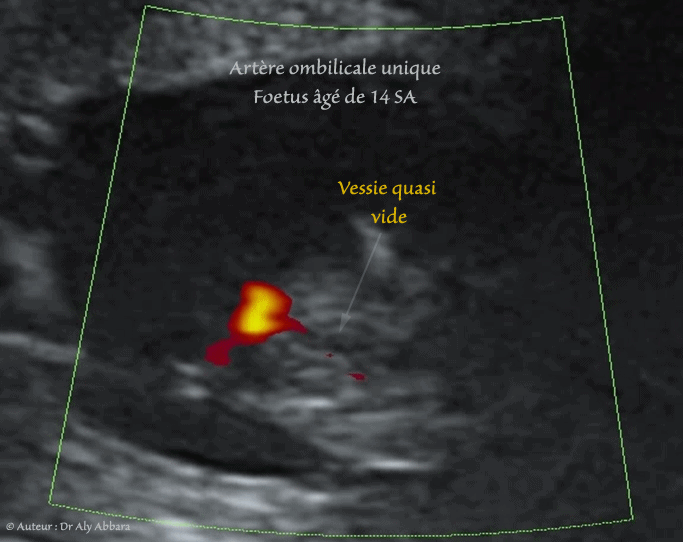

- Image échographique animée montrant, grâce au Doppler couleur de type Dynamic-Flow, la présence d'une artère ombilicale unique (AOU) dans sa portion pelvienne, coiffant la vessie après sa naissance de l'artère iliaque interne.

Il s'agit d'un foetus âgé de 14 SA, ne présentant pas par ailleurs, d'anomalie notable détectable à ce stade de grossesse.